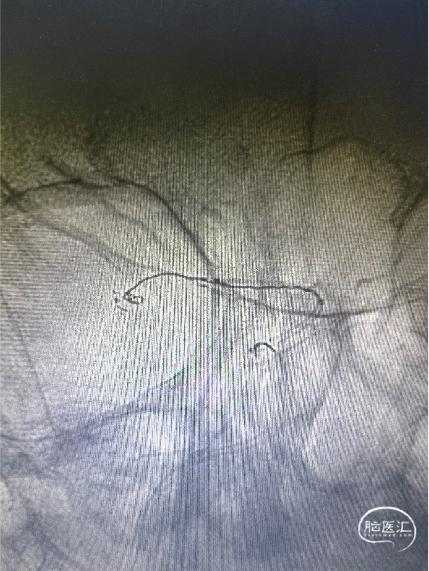

大脑中动脉下干置入3*24mm Atlas支架,使用Target 360 Ultra 2mm*4cm;弹簧圈栓塞动脉瘤。行造影观察血流通畅。(如下动态影像)

穿第一枚支架网眼于上干置入3*15mm Atlas支架

使用第二枚弹簧圈Target 360 Nano 1.5mm*4cm栓塞动脉瘤,造影显示动脉瘤瘤腔内有滞留,考虑到是未破裂动脉瘤,故结束手术。(如下动态影像)

将Atlas支架全部释放(如左动态影像)

Target 2mm*4cm弹簧圈成篮满意,支架打开良好。